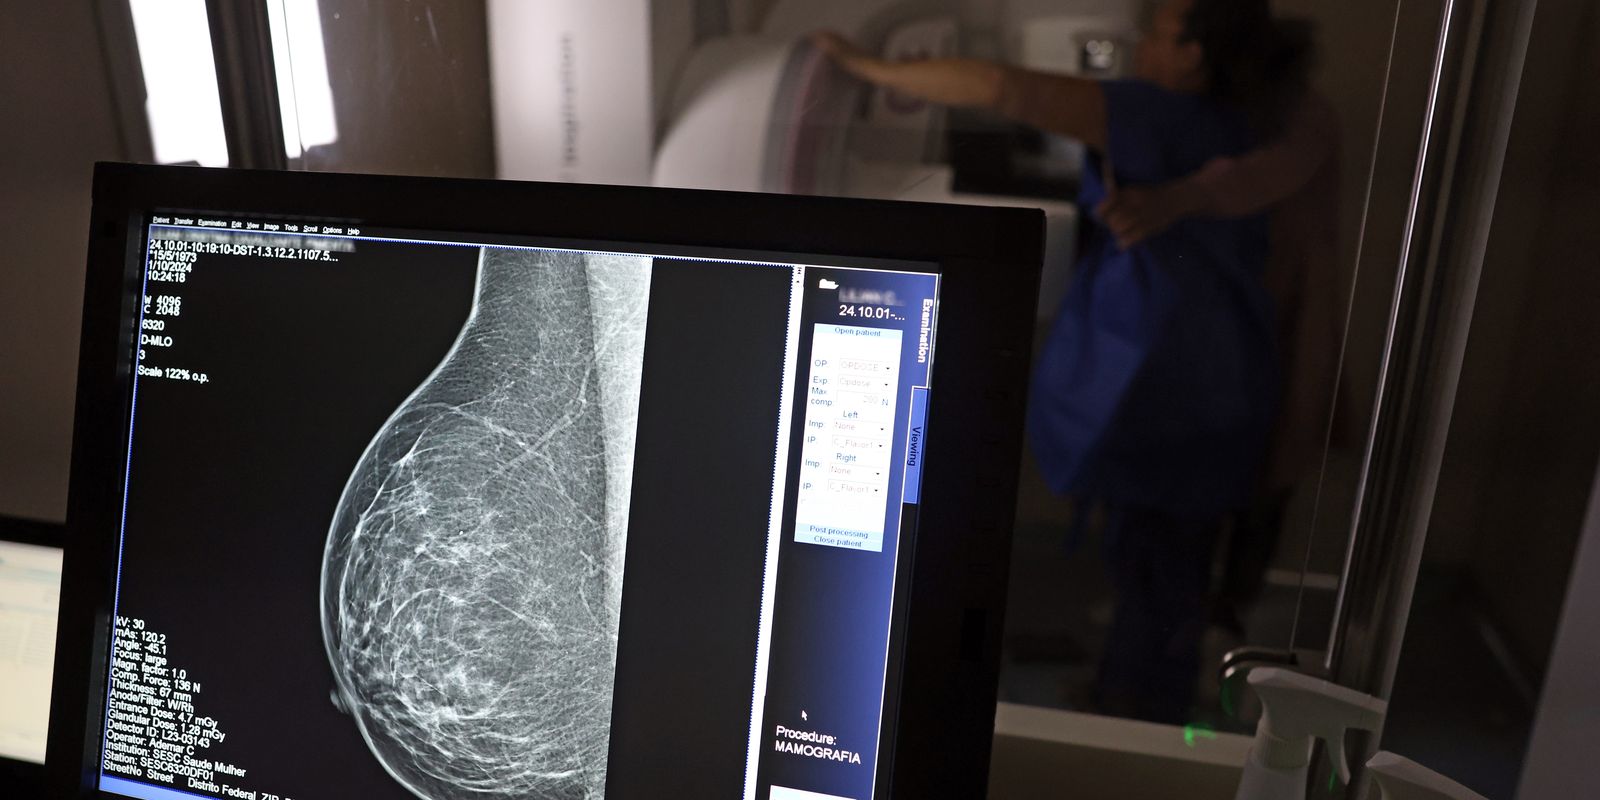

Mas, chegou a hora dela realizar a mamografia bilateral. Lilian Cristina se posicionou em pé, em frente ao aparelho e, imóvel, teve as mamas comprimidas em diferentes ângulos para captura das imagens detalhadas. No fim, ela saiu da carreta do Sesc com impressões positivas sobre o exame. “Achei que doía mais, mas foi bem tranquilo. Agora, espero ansiosa pelo resultado do exame.”

André Abreu, do Sesc-DF, explica que as imagens em alta resolução captadas pelos mamógrafos são enviadas automaticamente aos profissionais do Hospital de Barretos (SP) para análise e emissão do laudo médico, em até 30 dias. “Se o laudador já identificar visualmente um câncer, ele avisará a equipe de Brasília que poderá ter que repetir o exame e esta deverá encaminhar a mulher examinada como paciente ao Hospital de Base de Brasília”. Nos demais casos, quando for constatada a normalidade das mamas, a mulher receberá o laudo em um envelope nominal no prazo citado, no mesmo local – a rodoviária do Plano Piloto.

O técnico em radiologia Ademar Cardoso revelou que, nos dez anos de atuação na área, muitas vezes percebeu a presença de nódulos nas mamas de pacientes ainda no momento de realização da mamografia e comenta a relevância da prevenção. “Muitas vezes vejo pessoas sem informação e, por isso, o exame de graça é tão importante, porque é feito o encaminhamento necessário e a paciente pode dar início a tratamento, quando for o caso.”